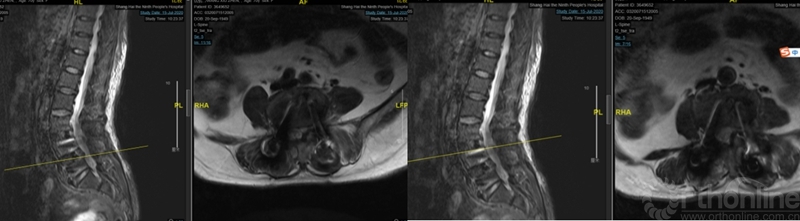

观察24小时后无明显改善,再次行开放腰椎全椎板扩大减压术,近端矢状面扩大减压延伸过腰椎矢状面顶椎(图8),左侧腰4、5及骶1神经根管扩大减压,直至肉眼辨别无明显交界区卡压和神经根紧张(图9)。

图8:第二次减压近端延伸至腰2椎体后方,保留腰1-2小关节完整

图9:第二次减压腰2至腰5全椎板减压,腰2-3小关节保留

第二次术后,患者的双下肢症状即明显的开始进行性恢复和改善。